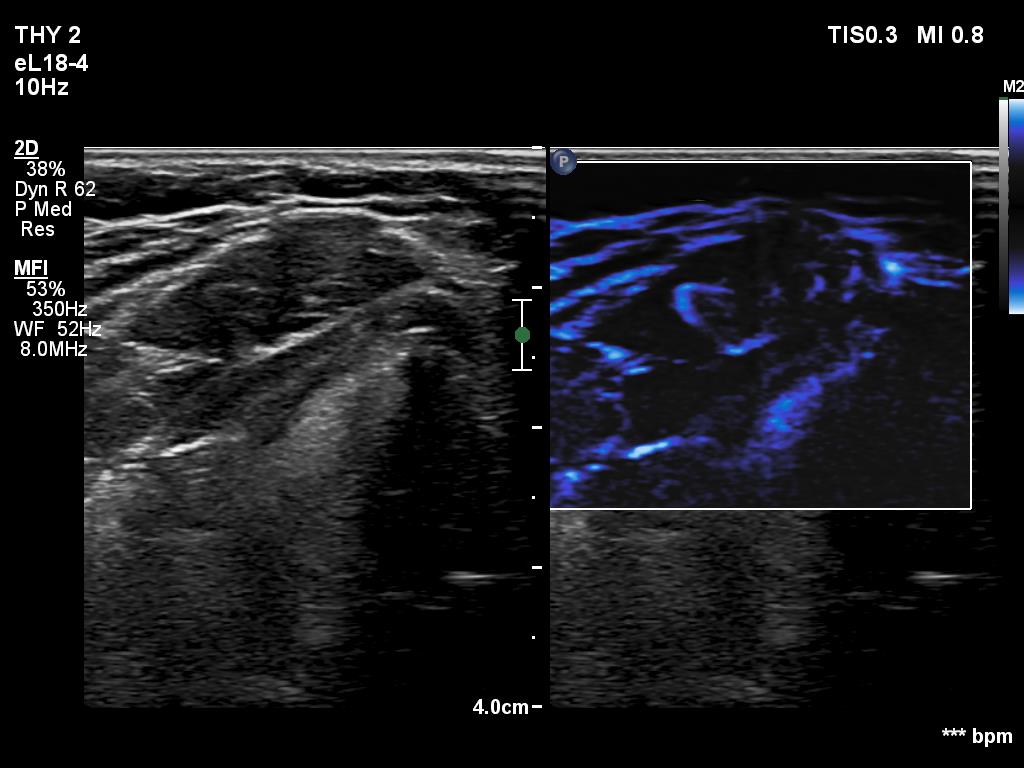

Graves' disease - case 940

Follow-up investigation 6 months after first visit (ultrasonographic picture 8)

Middle part of the neck, 4 cm above the thyroid, longitudinal scan, microflow imaging. The lesion has vessels.